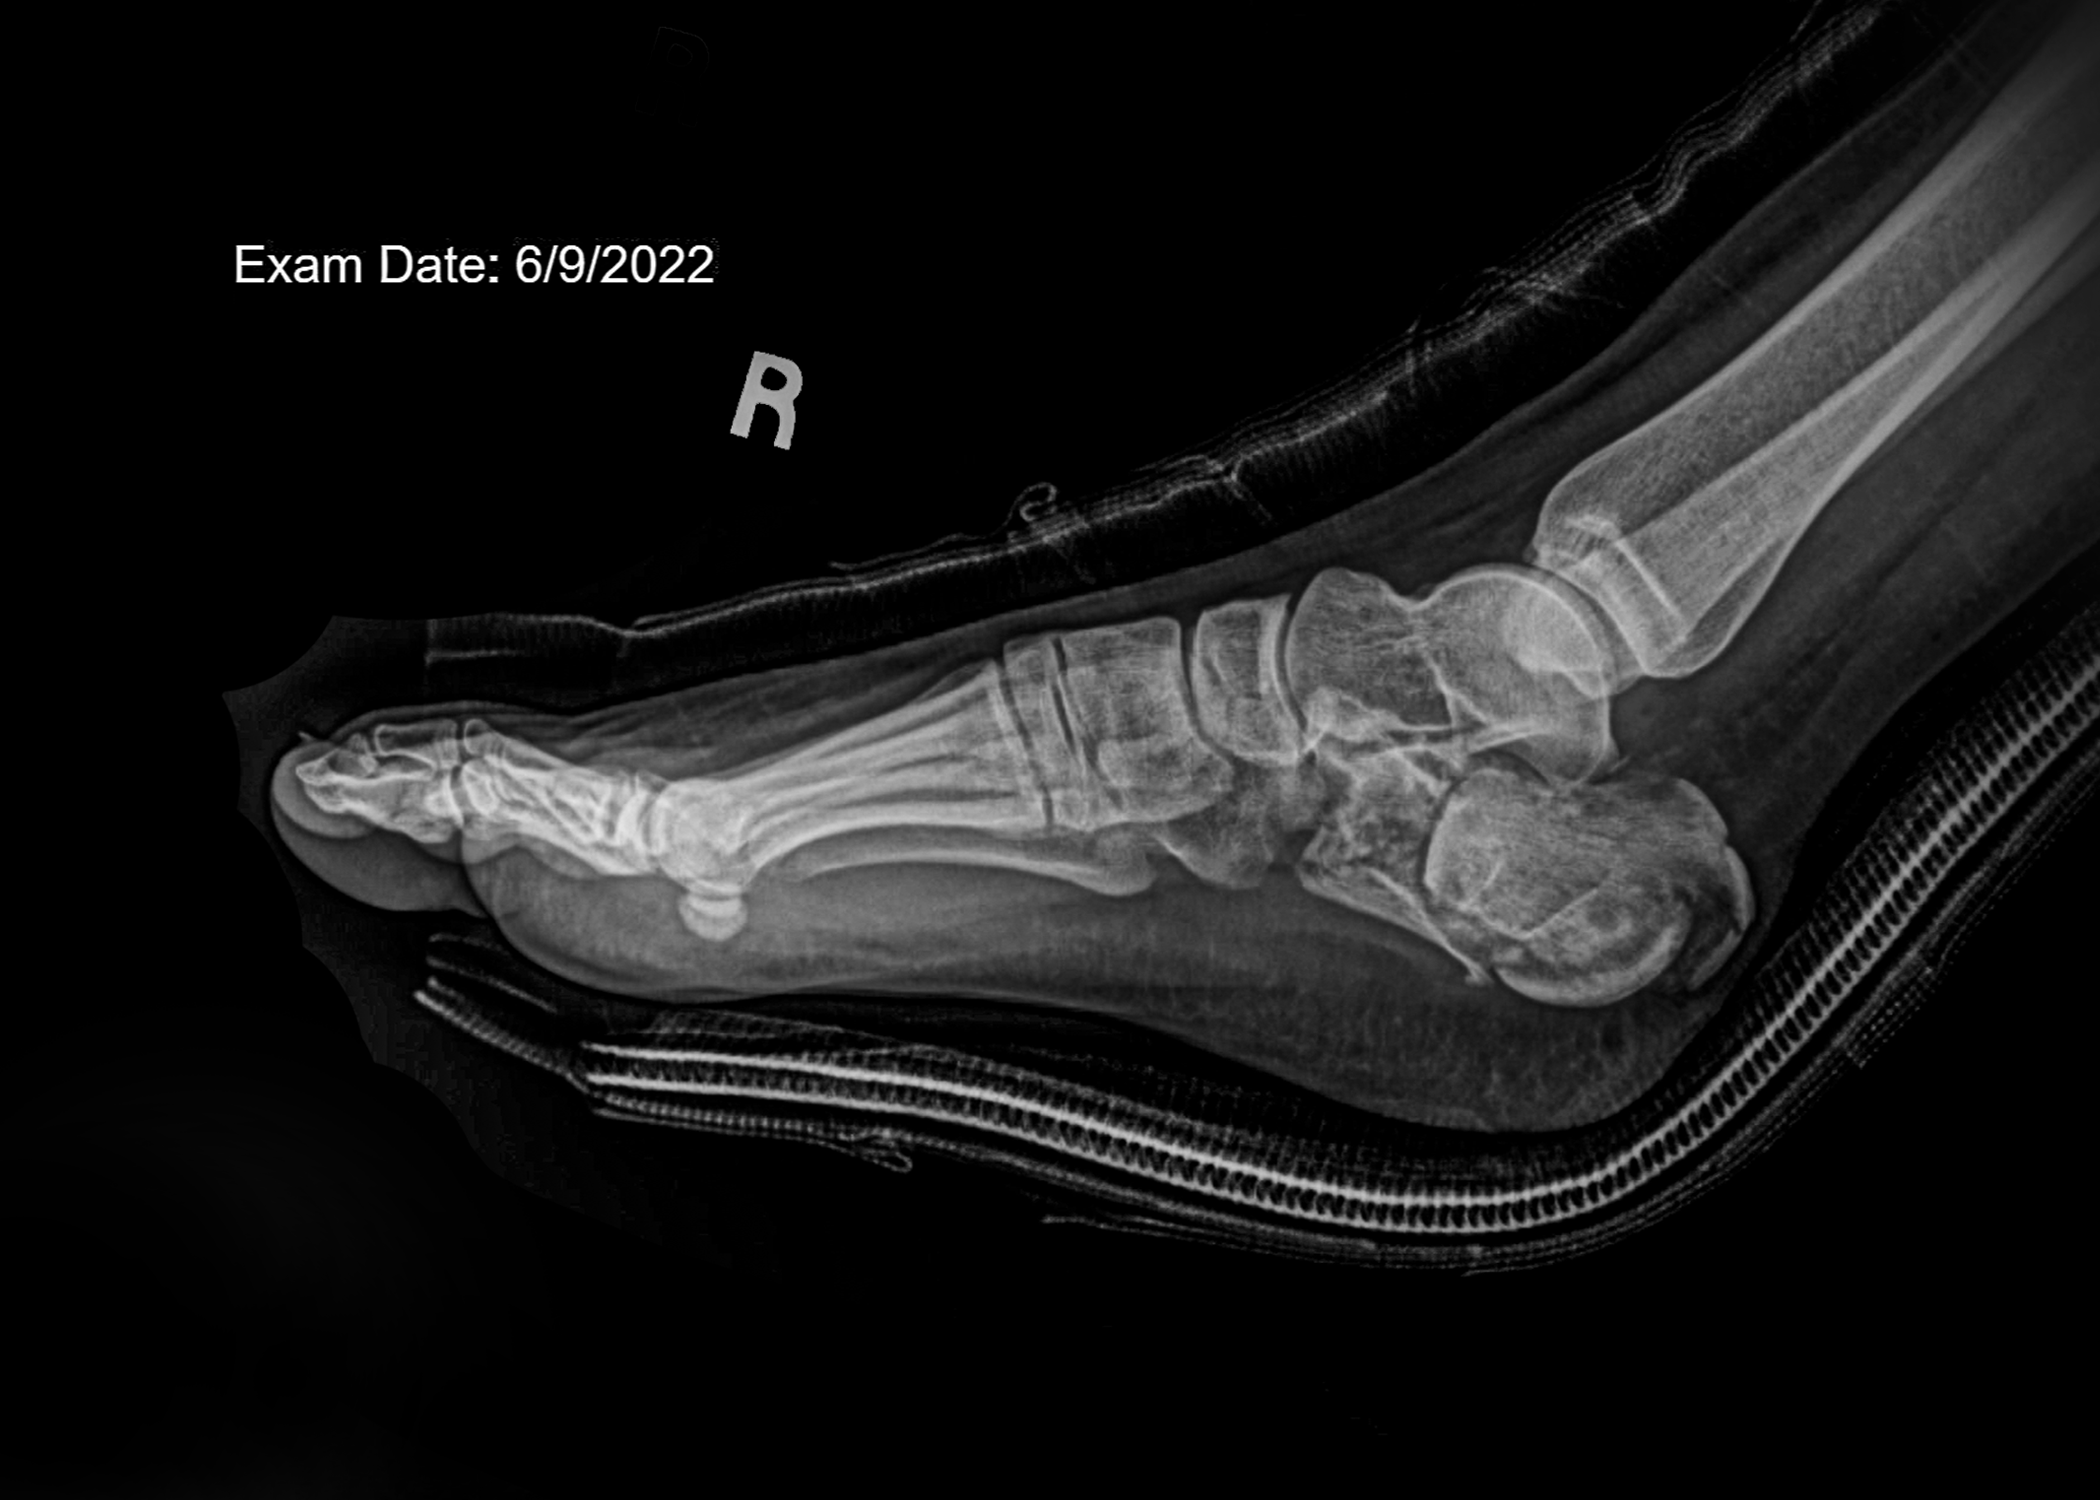

faux flowers X-rays, and tape installation

“Those sounded like terrible memories to have. I wonder if they will ever come back. I hope they don’t” -6/14/2022. Although my memories from the fall never came to me, the aftermath can never be forgotten. More than anything, I wanted to find meaning in my accident.